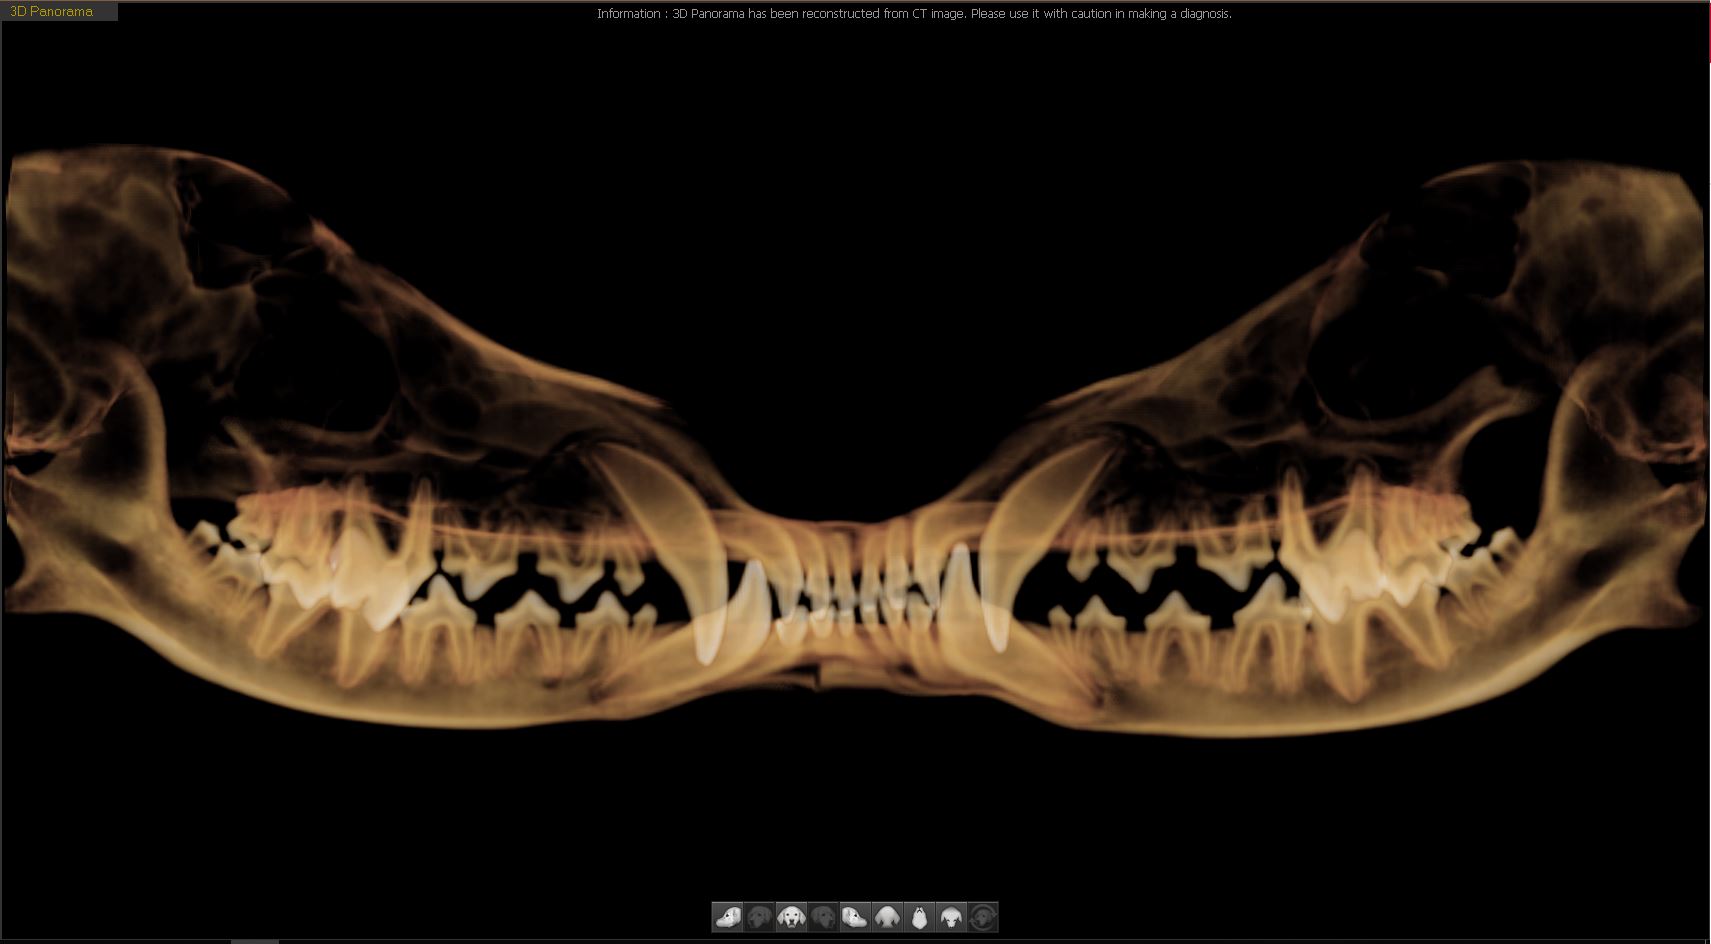

치과파노라마 CT

치과파노라마